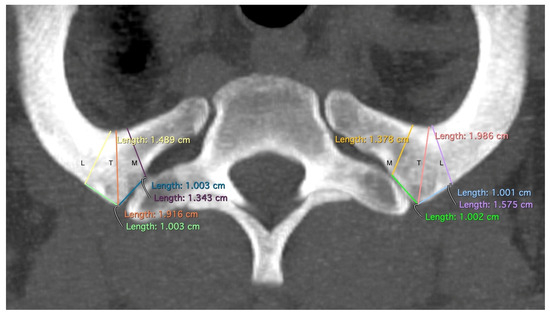

| Variable Name | Abbreviation | Description |

|---|---|---|

| Tuberculum | T | The minimal width of the rib at the level of the tuberculum costae 1 |

| Medial | M | The minimal width of the rib 1 cm medial to the tuberculum costae 1 |

| Lateral | L | The minimal width of the rib 1 cm lateral to the tuberculum costae 1 |

| Rib width | R | Minimal width of the rib at the height of the front edge of the first thoracic vertebral body. |